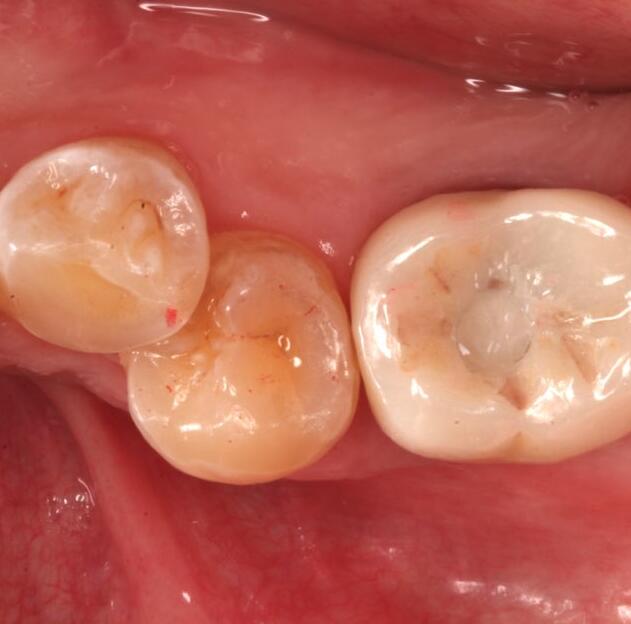

活動(dòng)義齒是一種可自行摘帶的牙齒修復(fù)的方法,選擇活動(dòng)義齒來恢復(fù)牙齒的使用狀態(tài),是因?yàn)檫@種調(diào)節(jié)方式對(duì)我的口腔損傷比較小。在做完手術(shù)后,不會(huì)感覺我的牙齒有不舒適的情況,而且平時(shí)自己就有戴假牙的習(xí)慣,所以做活動(dòng)義齒反而會(huì)覺得更方便,更適應(yīng)一些。在做活動(dòng)義齒的調(diào)節(jié)時(shí),我對(duì)活動(dòng)義齒的材料沒有過敏反應(yīng),并且因?yàn)槔钚γ丰t(yī)生的牙齒修復(fù)調(diào)節(jié)的手法嫻熟,我在做了牙齒的調(diào)節(jié)后,沒有出現(xiàn)其他不良的情況。